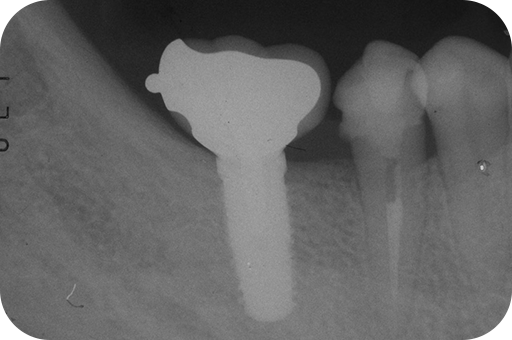

右下5番 感染根管治療

- 右下5番

- 感染根管治療

- 再根管治療の場合(一度でも根管治療を行った歯)は根管内が細菌により汚染されています。根管内の汚れをきれいにしていくと根管壁が薄くなるため強固に硬化し、持続的な殺菌作用を持つ特殊なセメント(MTAセメント)で充填する場合があります。MTAセメントを使用することにより、条件の悪い歯でも保存が可能な場合があります。治療の過程で判断致しますので、必要な場合は別途料金が発生致します。